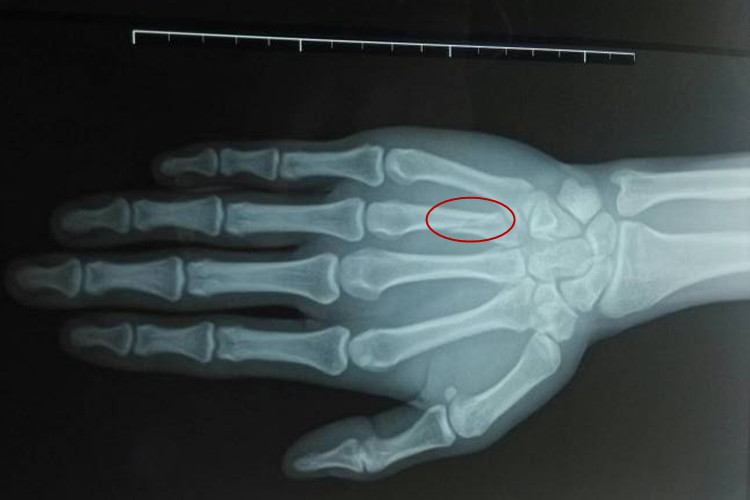

- 儿童骨骼生长较快,修复能力强。若骨裂部位稳定,且为非负重部位,如上肢的轻微骨裂,15天有可能达到初步愈合,可以考虑拆除石膏,但仍需医生评估。

- 对于身体健康的成年人,若骨裂发生在非关键部位,如手指、脚趾等,且恢复良好,15天可能接近愈合,但拆除石膏仍需谨慎,以防未完全愈合导致二次损伤。